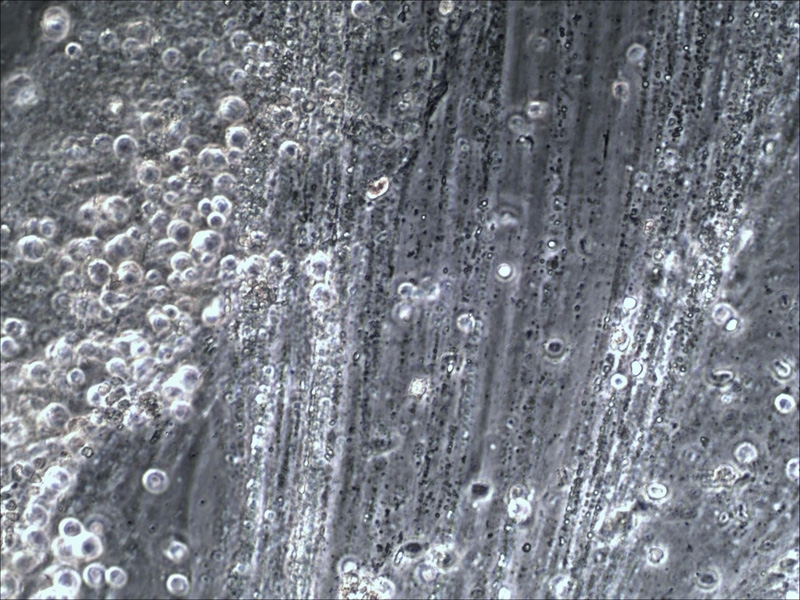

Schnappschuß 1: Hier weiß ich leider nicht mehr mit welchem Objektiv ich das geschossen hab. Was könnte das sein?

Schnappschuß 2: Das war ein 10er. Mich interessieren die vielen kleinen schwarzen Punkte. Bakterien?

Schnappschuß 3: Geschossen mit nem 10er. Viele, viele Zellen... aber noch net wirklich sichtbar was es ist...

Schnappschuß 4: 40er, jetzt kann mans erkennen.

Schnappschuß 5: 40er...

Schnappschuß 6: 40er...

Bin zwar nur Laie, aber für mich sind das schlichte Alveolarmakrophagen, also "Fresszellen". Nichts pathologisches, kommt bei jedem vor.

Jenachdem, was sie phagozitiert haben, nennt man sie auch Siderophagen (Blut) oder Koniophagen (Rußteilchen).